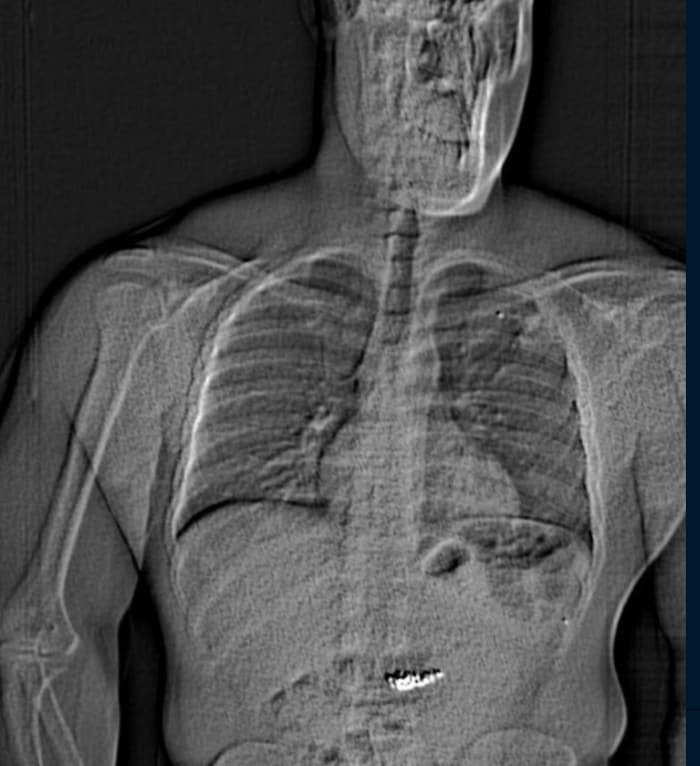

Die Beamten führten einen Körperscan bei dem Festgenommenen durch.

Die Beamten führten einen Körperscan bei dem Festgenommenen durch.(Bild: Orlando Police Department)

Die Beamten führten im Laufe der Ermittlungen einen Körperscan bei ihm durch. Laut des Senders WFLA „wurden dabei Fremdobjekte im Magen entdeckt, die von der Form her auf die gestohlenen Ohrringe passten“. So war es dann auch, die Ohrringe wurden wieder „zutage befördert“.